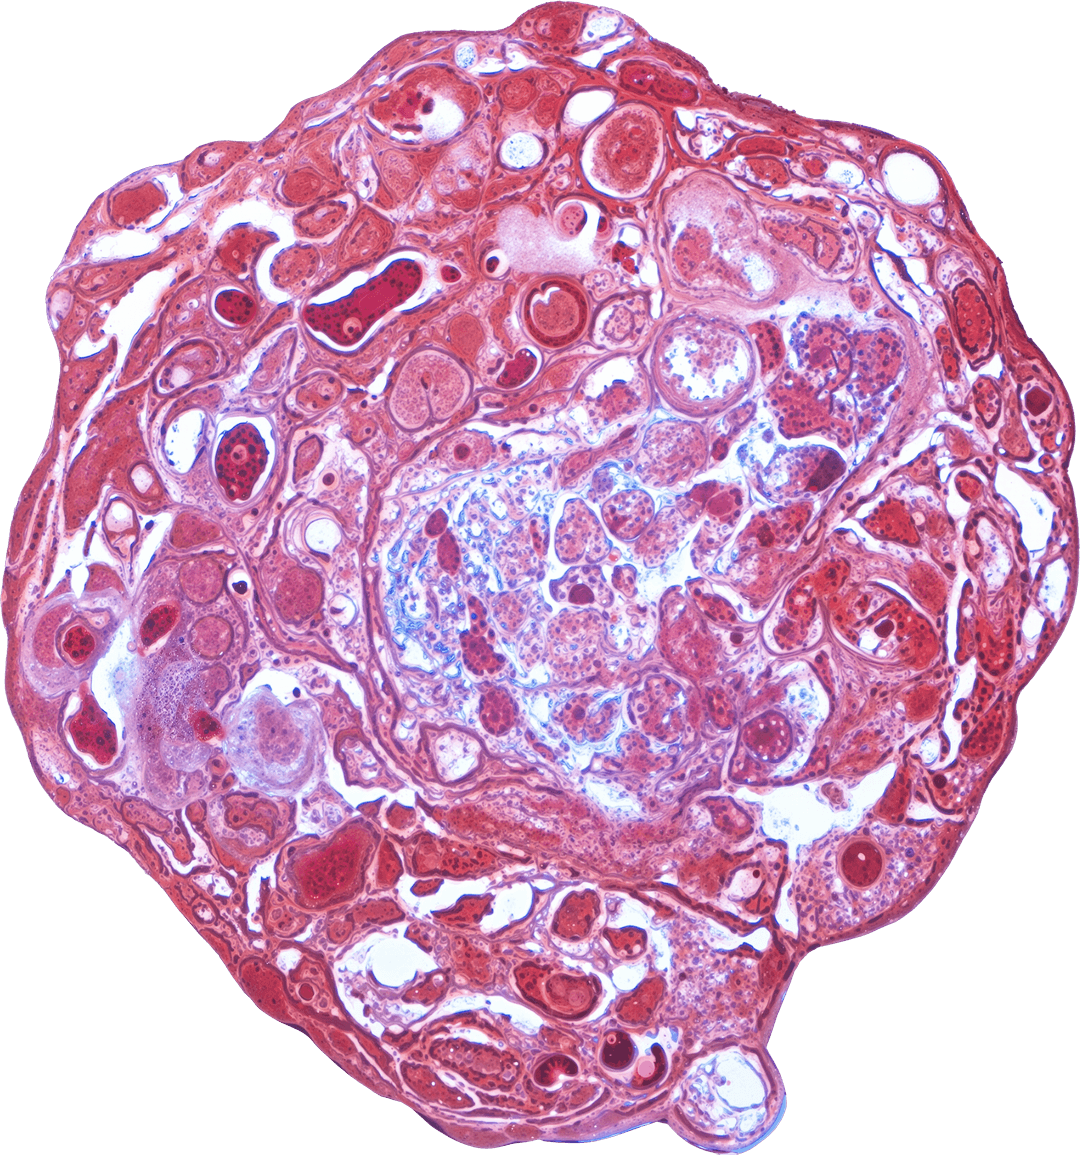

VitroScreen, a SenzaGen Group company, pioneers next-generation in vitro testing solutions. We leverage cutting-edge biological models—from 2D cells and reconstructed tissues to ex vivo systems and cellular spheroids—to deliver precise, human-relevant data for the Cosmetics, Medical devices, Nutraceuticals, Pharma and Chemicals industries.

Our models mirror human biology for precise, predictive accuracy.

We design and execute rigorous preclinical in vitro studies, combining validated testing standards with fully customized protocols to deliver reproducible, decision-ready results. Our expertise covers multiple product categories and therapeutic areas, providing highly predictive platforms for both regulatory and efficacy assessment.